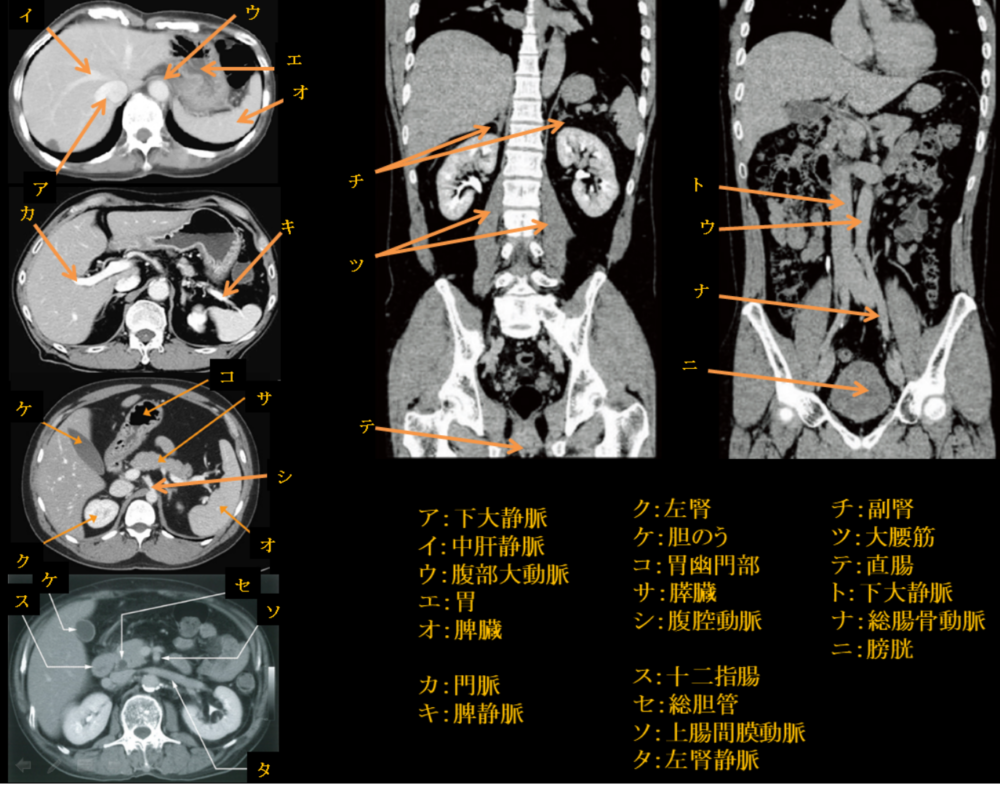

腹部血管のX線解剖図譜 平松京一 医学書院 絶版 医療/画像診断

腹部血管のX線解剖図譜 平松京一 医学書院 絶版 医療/画像診断

腹部血管のX線解剖図譜 平松京一 医学書院 絶版 医療/画像診断。腹部のCT 第2版 | 栗林幸夫, 平松京一, 栗林幸夫, 谷本伸弘。。

著者名:平松京一

出版社名:医学書院

発売日:1982年07月

ISBN:9784260134507

著者名:平松京一

出版社名:医学書院

発売日:1982年07月

ISBN:9784260134507